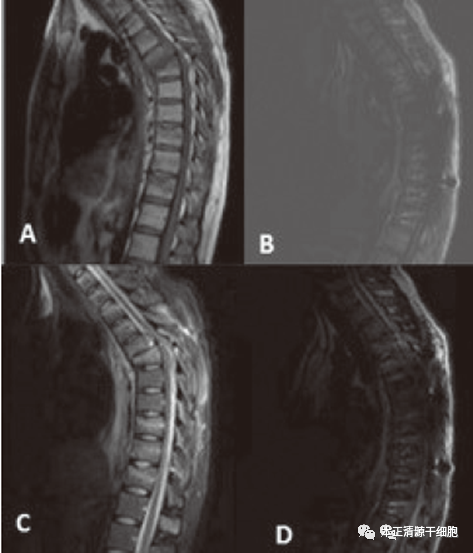

我国至少有约130万脊髓损伤者,并且以每年5至7万的速度增长。90%的脊髓损伤患者源于外伤所造成的,致双下肢或四肢瘫痪。像车祸伤、高空坠落伤、运动损伤、工地塌方等均可造成脊髓的损伤。 2、感觉障碍:脊髓损伤平面以下感觉的减退消失或感觉异常。 3、括约肌功能障碍:主要表现为膀胱括约肌和肛门括约肌功能障碍(尿潴留、尿失禁、排便障碍)。 4、自主神经功能障碍:排汗功能和血管运动功能障碍。 5、颈段脊髓损伤:四肢瘫;胸、腰段脊髓损伤:截瘫。 6、日常生活能力障碍:吃饭、如厕、穿衣、转移等功能障碍。 因为神经细胞几乎无再生能力,神经系统修复损伤及重建功能的能力较为有限,所以,脊髓损伤要恢复往往是很困难的。当前治疗创伤性脊髓损伤的方法是手术减压脊髓和内科治疗,如甲基强的松龙类固醇治疗。但当前治疗方法治标不治根,无法让患者恢复脊髓损伤丢失的功能。 近年来,以干细胞为基础的再生医学正在不断呈现其独特优势,其中间充质干细胞(MSCs)以其强大的自我复制、多向分化和免疫调节特性,在神经系统疾病的治疗研究中大放异彩,为脊髓损伤带来了新的治疗方向。 近年来,干细胞治疗脊髓损伤的成功案例在国内外相继被报道。日前,土耳其研究团队报道了1例29岁创伤性脊髓损伤患者接受脐带间充质干细胞治疗后获得恢复的案例。相关结果发表在 Turkish Neurosurgery杂志上。 2021年,在得到土耳其卫生部批准后,Serdar Kabataş等学者开展了间充质干细胞(MSCs)治疗一名29岁男性创伤性脊髓损伤患者的试验。 这位患者从电线杆上摔下来后被送往医院的急诊室,被诊断为中胸(T5-6)骨折脱位和钝性创伤性脊髓损伤,相当于患者骶骨及以下区域没有运动及感觉功能。 在受伤后6小时内接受了手术,并接受了T5-7全椎板切除和T3-11后外侧融合。令人遗憾的是,手术后患者的神经状况并没有发生改变。术后,患者接受了3个月的物理治疗,但在详细的神经学检查中并没有观察到运动恢复或骶骨部位感觉改变。 在这个阶段,患者选择接受间充质干细胞治疗。治疗前,患者进行常规检查,且符合如下条件:病情稳定,没有全身麻醉禁忌症,没有任何严重感染性疾病。治疗方案:鞘内、肌肉和静脉注射间充质干细胞,每隔两周一次,共四次。治疗期间,以及治疗结束后,进行为期1年的长期随访评估。 患者在接受间充质干细胞治疗后的随访1年间,患者多层面如感觉、运动、生活质量、安全等,都获得了很好的运动恢复效果,证实了间充质干细胞治疗创伤性脊髓损伤的疗效及安全性。 1、干细胞输入患者体内后,可分化为神经元星形胶质细胞和少突胶质细胞,达到在结构和功能上的修复或替代,同时产生多种细胞外基质,填充脊髓损伤后遗留的空腔,为再生轴突提供支持物。 2、干细胞输入受损脊髓后分泌的多种神经营养因子通过激活体内处于休眠及受损神经细胞,来实现神经保护功能。 3、干细胞能使神经纤维形成新的髓鞘,保持神经纤维功能的完整性,从而促进损伤的功能恢复。 综上所述,干细胞治疗在损伤脊髓的功能恢复方面展现出了巨大的潜力,相信在广大科学家的不懈努力下,再生医学在未来能够在脊髓损伤治疗这一世界医学难题中,发挥独特与创新的作用,为脊髓损伤患者带来新的希望。